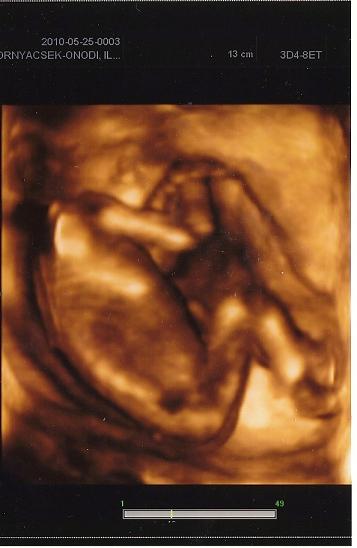

Kicsi bújós Luca babánk